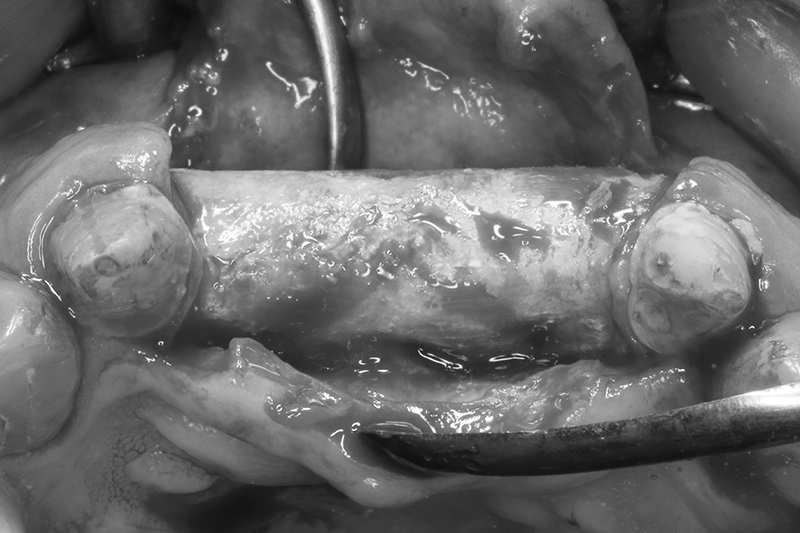

取出的舊有one piece植體,舊式植體。